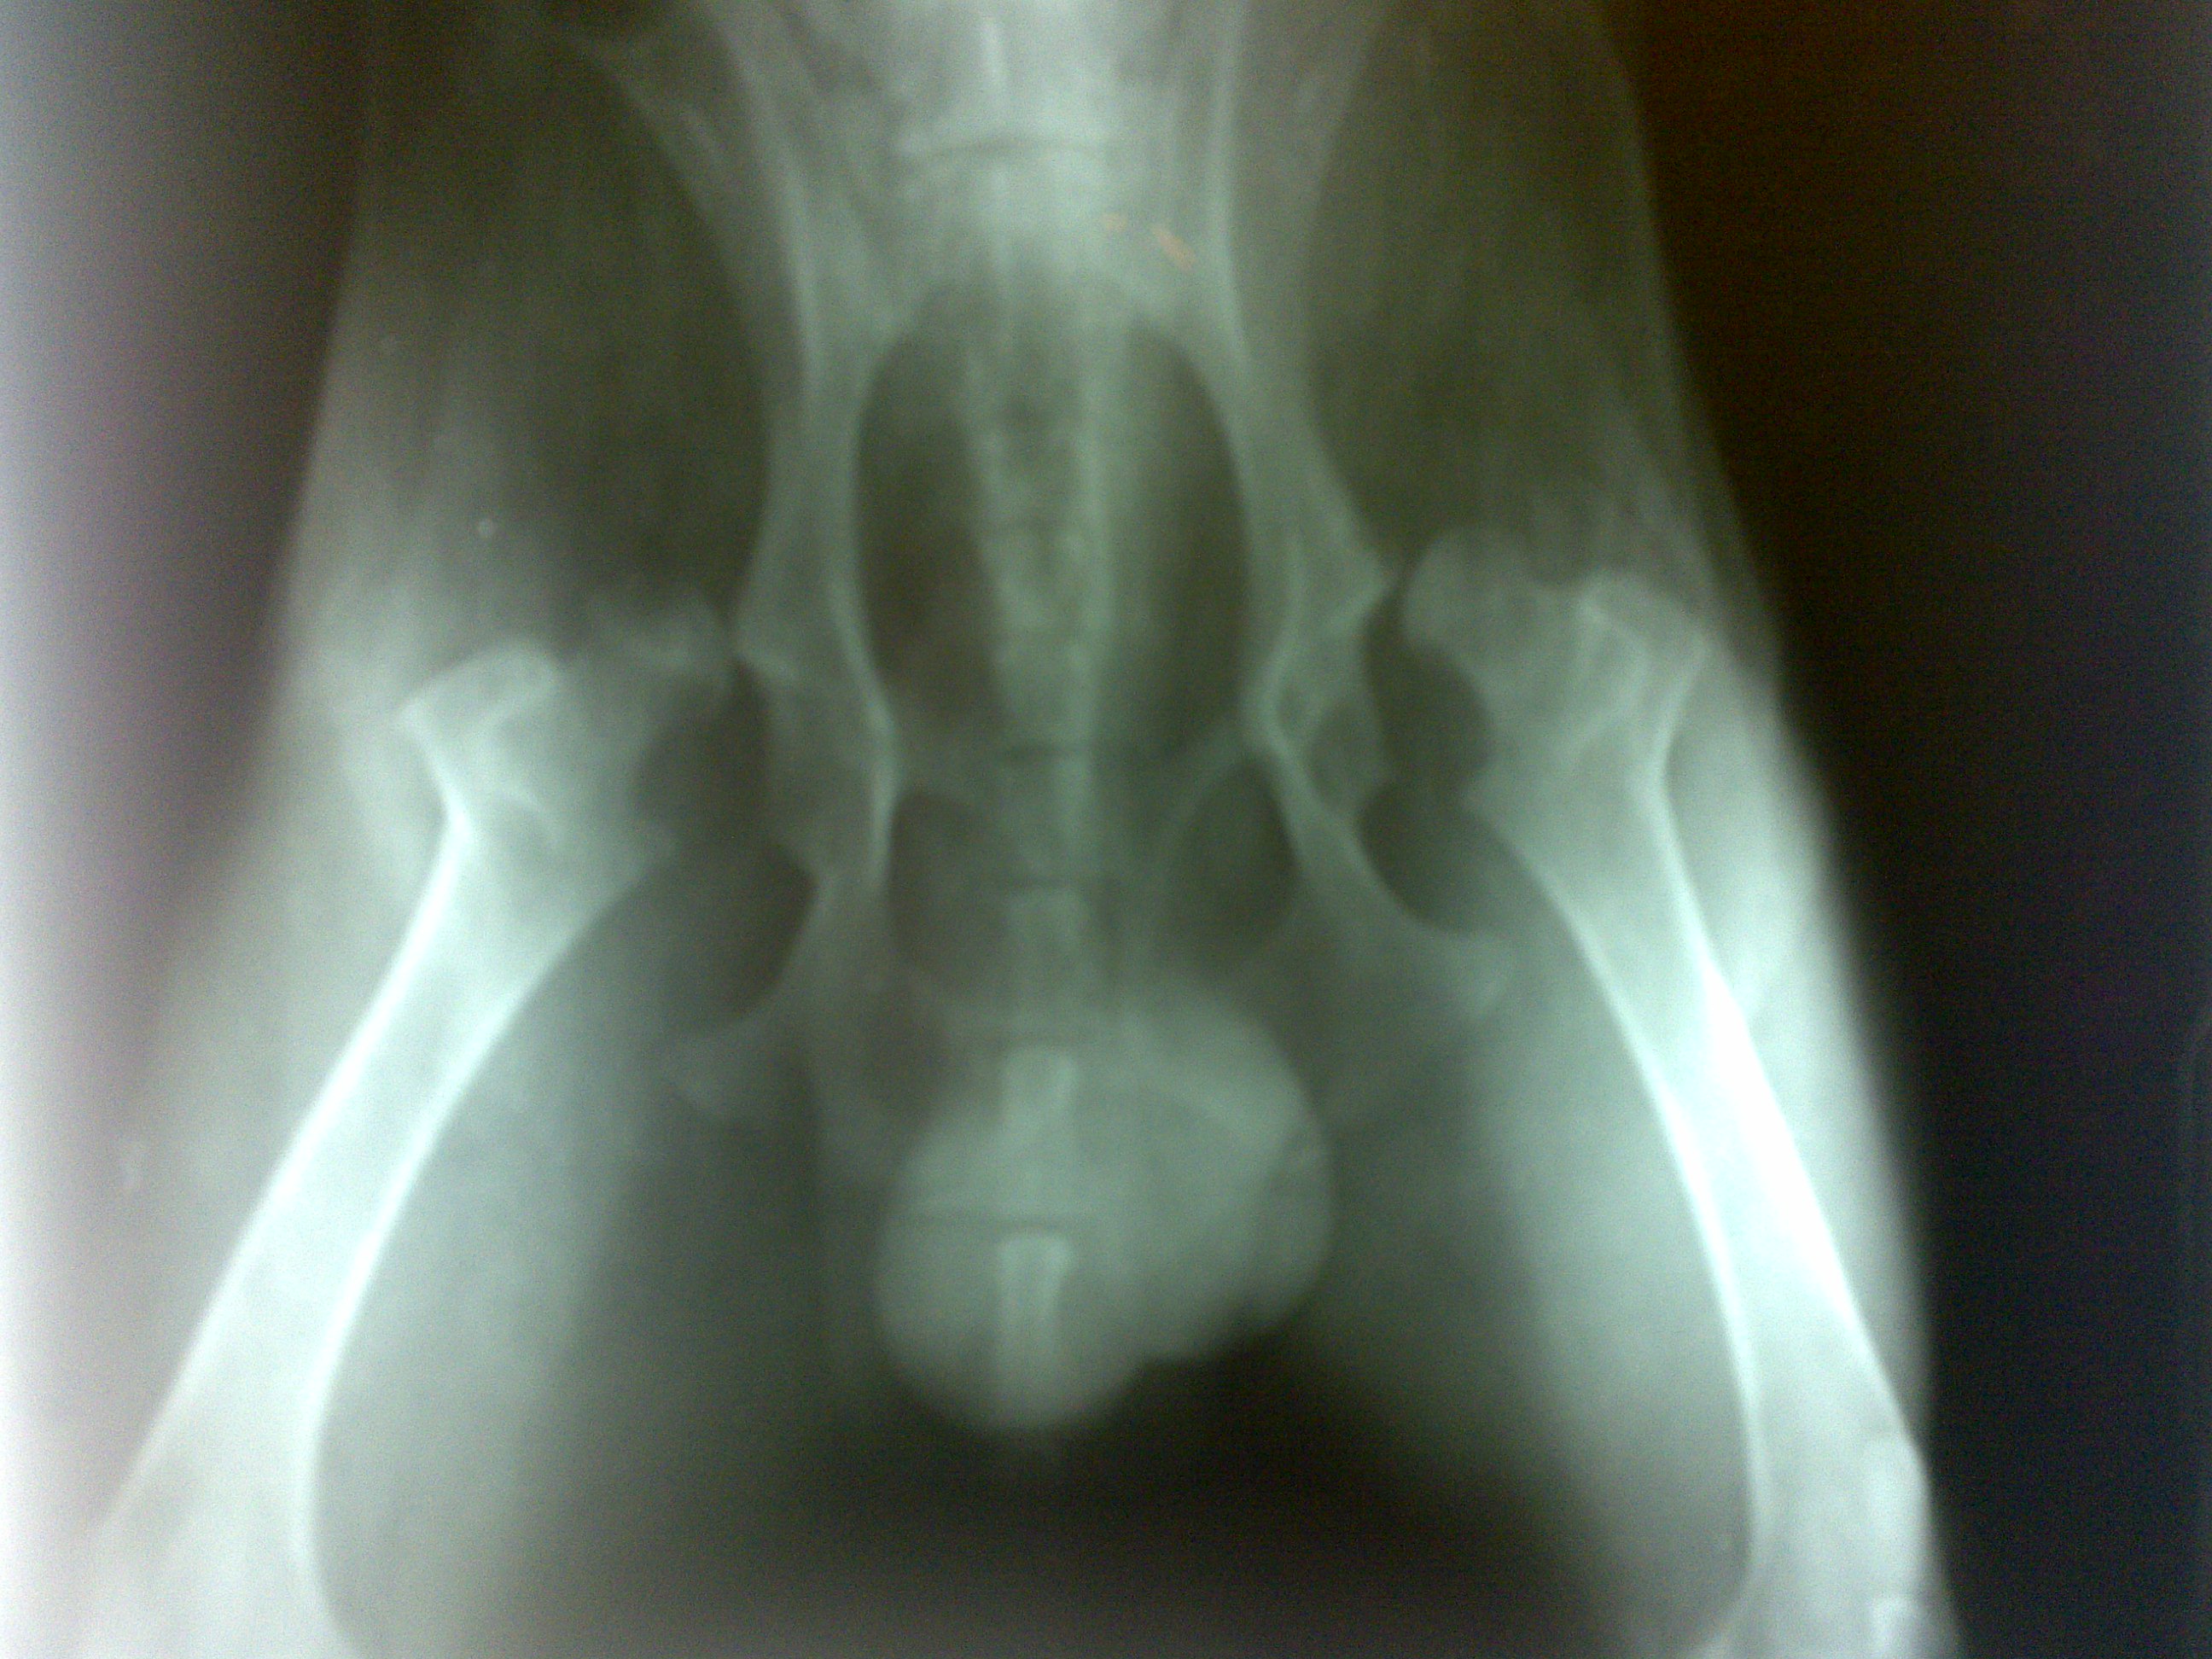

Displasia bilaterale dell'anca in cane labrador